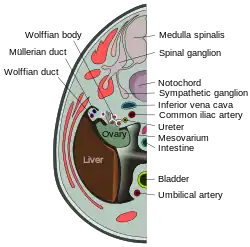

Transverse section of human embryo eight and a half to nine weeks old. (Mesovarium visible at center.) | |